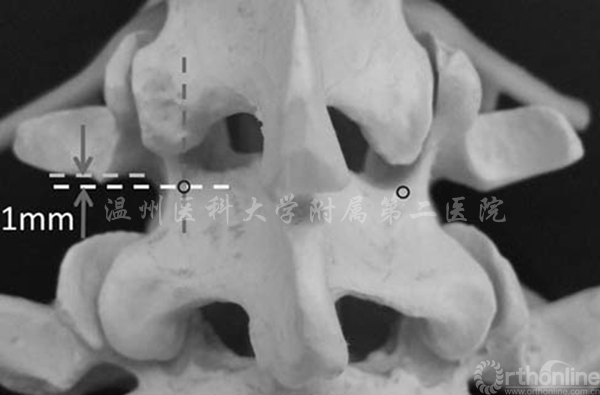

Ivanov等人发现峡部的厚度从内侧至外侧边缘逐渐增加,而进针点选择在为上关节突中线与横突下1mm之间的交点,大致位于峡部外侧缘向内3mm左右,正好位于椎体背侧皮质骨且接近峡部外侧处(图2)[3]。

图2 进针点(圆圈标记)为上关节突中心与横突下缘1mm的交点(相当于峡部外侧壁内3mm处)